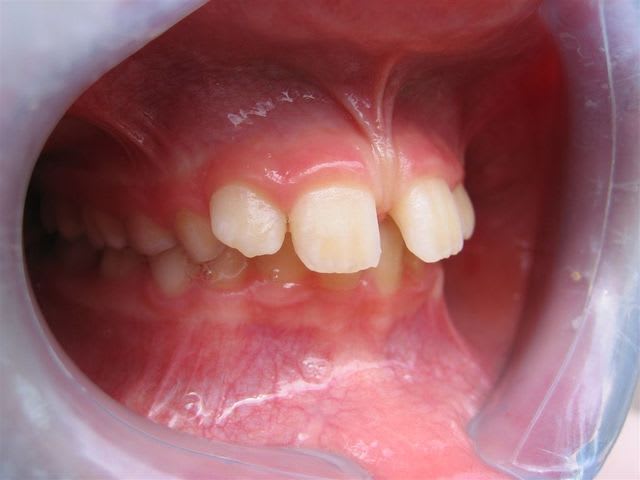

... ma gamine, bientôt 9 ans.

Père CD ... traitement d'ortho.

Mère CD ... traitement d'ortho.

Les conseils sont les bienvenus.

C’est un cas simple ou il faut juste stimuler un peu la croissance et reformer les arcades.

C’est le type même du traitement d’interception en denture mixte.

... elle est en classe I, avec une grosse supra.

TT "fonctionnel" prévu dans qqs semaines.

... c'est en cours ... un appareil de chez Rocky Mountain va être mis en place, à porter environ 16 heures/jour; il va falloir que je m'en fasse expliquer le principe lors de la séance de pose.